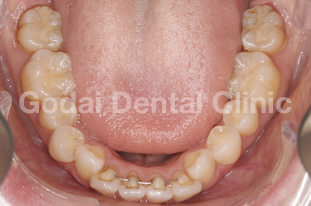

患者様は20代女性、むし歯の治療と歯並びを改善したいという主訴で来院されました。口の中を診査していくと、奥歯に装着された古い金属の下がむし歯になっていました。また下の前歯がガタガタになってきていること、前歯が出てきたことを患者様は気にしていました。むし歯については、審美性・耐久性・生体親和性を考えセラミックス治療を行い、歯並びの改善はマウスピースを用いたインビザライン矯正治療を行うことになりました。

まずはセラミックスを用いてむし歯の治療を行いました。その後、インビザライン矯正治療に移行し、約1年の移動期間で治療を終えることができました。金属を外しセラミックスで治療したことで口の中が明るくなり、矯正治療により上の前歯が出ていることと下の前歯のガタガタを改善することができました。歯並びが良くなることで将来的にむし歯と歯周病のリスクを下げることができますし、ステインも付着しにくくなるので今後のメンテナンスをやりやすくなるのが大きな魅力です。

治療前4

治療後4